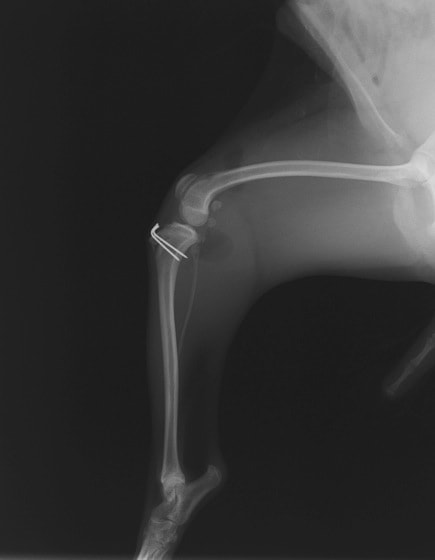

■ 症例22 ポメラニアン 1歳5か月 去勢雄

左後肢の挙上を主訴に来院した。整形学的検査、レントゲン検査より左右の膝蓋骨脱臼(左GradeⅡ〜Ⅲ、右Grade Ⅱ)を認めた。また、脛骨の前方引き出し試験の際に、引き出し兆候は認められないものの、疼痛が認められたため、前十字靭帯の損傷が疑われた。術中における、目視および関節内の操作によって、前十字靭帯の損傷や過伸展といった異常が認められなかったため、膝蓋骨脱臼の整復のみ実施した。手術手技は縫工筋及び内側広筋の解放、脛骨粗面の外側転位、滑車ブロック形造溝術、内外側関節包の縫縮を実施した。本症例は跛行もなく経過良好である。しかし、頸骨高平部の角度(TPA)が 右26.2°、左24.9°であり、解剖学的に前十字靭帯損傷のリスクが高いことから今後の経過に注意が必要である。